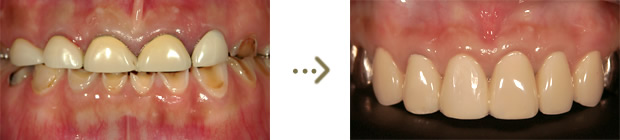

CASE4 歯周外科(歯冠長延長術)

治療前・治療後の写真です。 歯周外科(歯冠長延長術)を全顎的に行い、レジン前装鋳造冠にて修復しました。